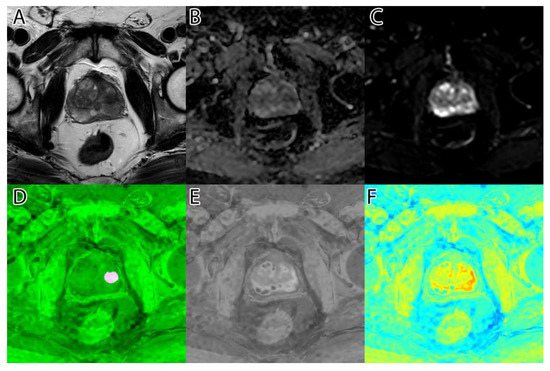

The second step was to compute the inversion of T2WI and ADC, thus obtaining the area of interest (tumor) represented by higher intensity values, as seen in Figure 1D,E. For this, we subtracted the actual image values from the maximum of 255.

Figure 1. Sample image: (A)—T2WI; (B)—ADC; (C)—DWI; (D)—inverted T2WI; (E)—inverted DWI; (F)—RGB images resulting from image fusion of (CE).

The third step was to combine the three images into an RGB (red, green, blue) image. T2WI was used for the red channel, ADC was used for the green, and DWI was used for the blue. The resulting image can be seen in Figure 1F.

The algorithm was used on all 204 images and computed the tumor intensity image. A sample from the original data, and the resulting fused image, can be seen in Figure 1.